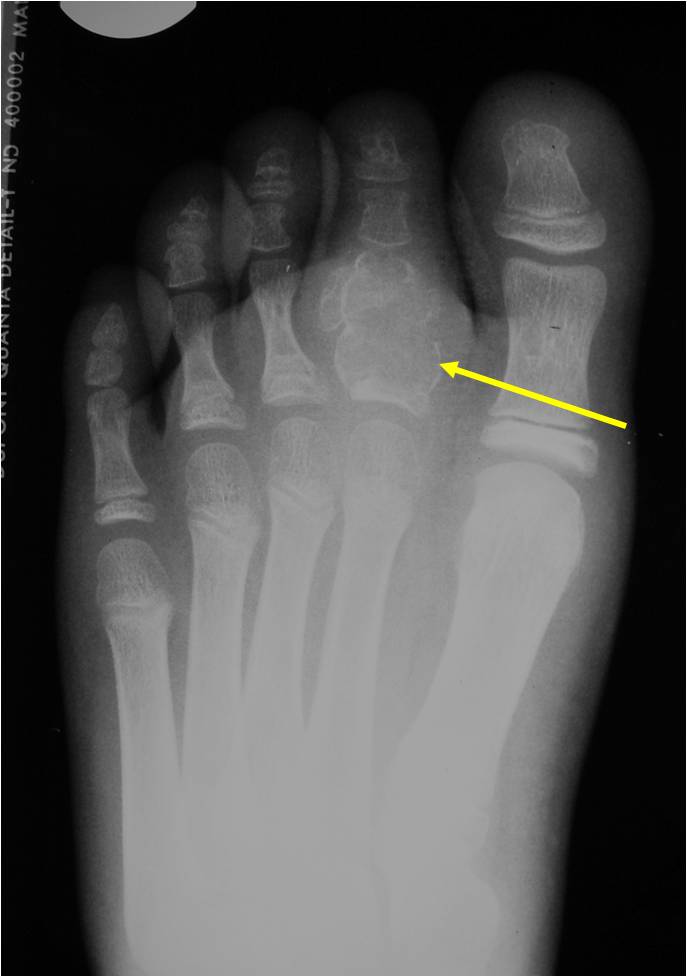

General Information Enchondroma is a benign indolent intramedullary hyaline cartilage neoplasm Accounts for 10% of all benign osseous tumors Limited growth, most lesions are less than 5 cm in maximal dimension Bones grow from a cartilaginous growth plate that...